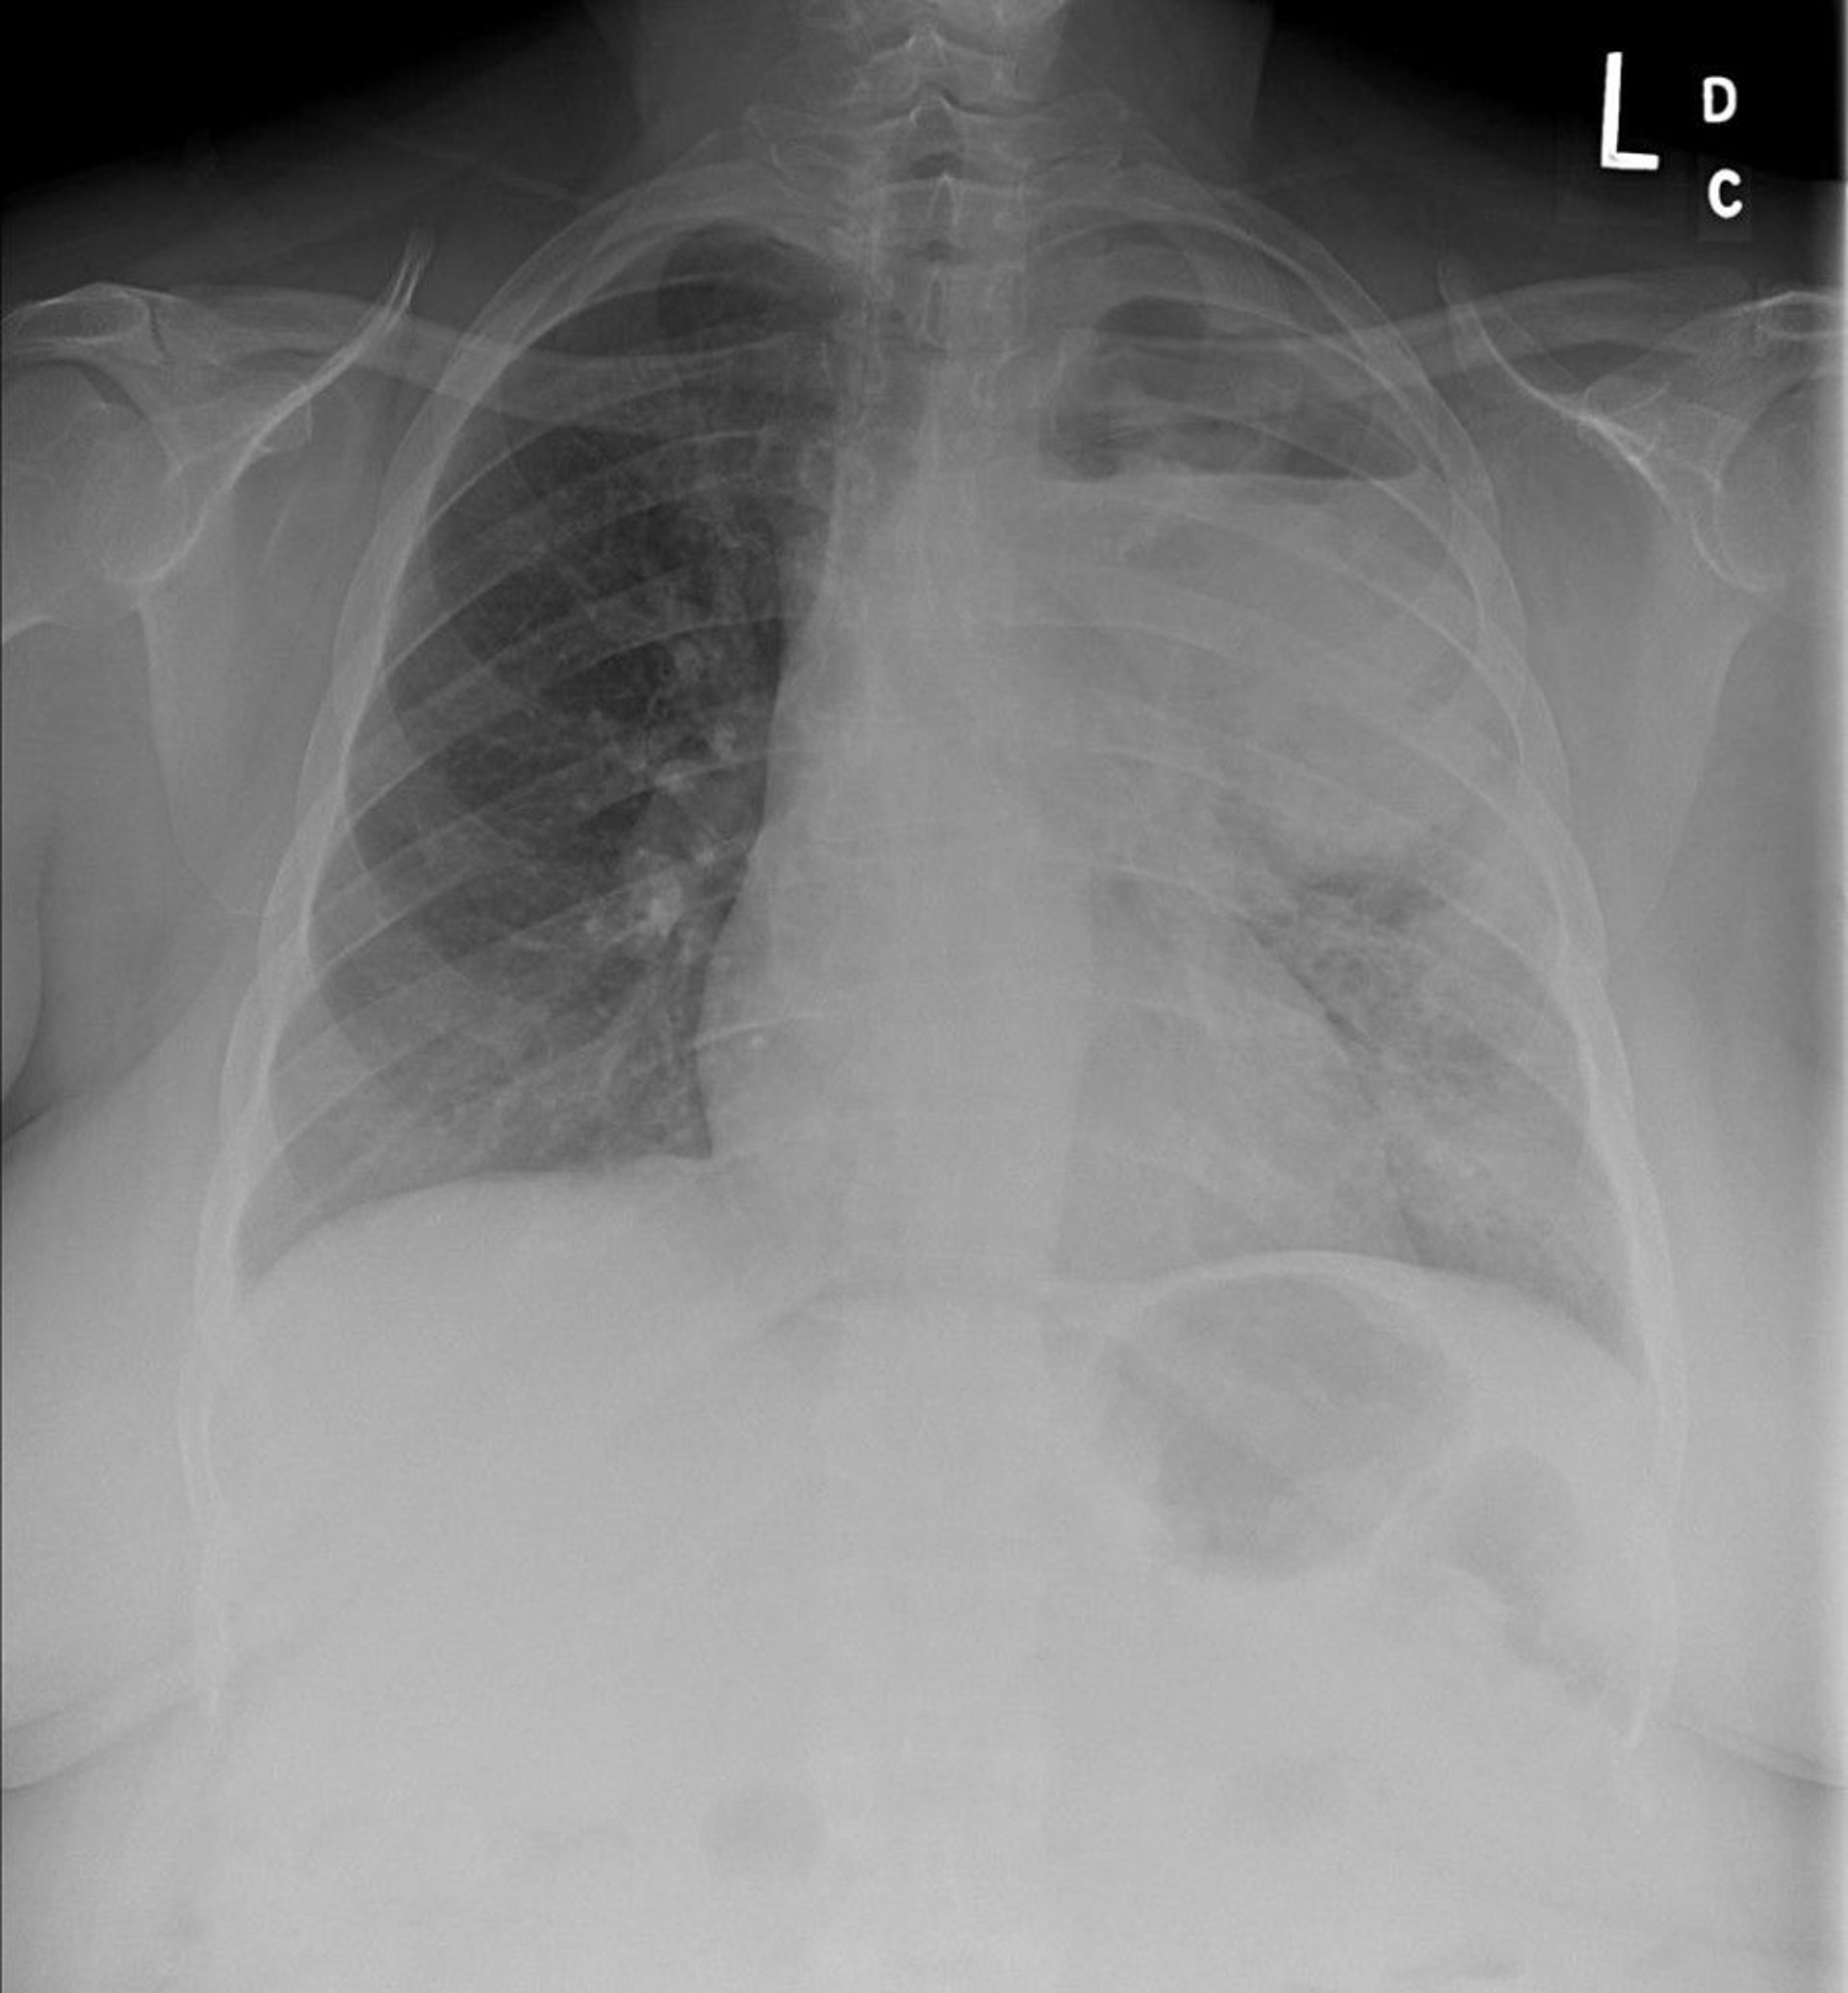

Chest x-ray shows a left upper lobe non–small cell lung cancer with mediastinal and left hilar adenopathy. The primary tumor is cavitated and an air-fluid level is present.

Image courtesy of Anne S. Tsao, MD.